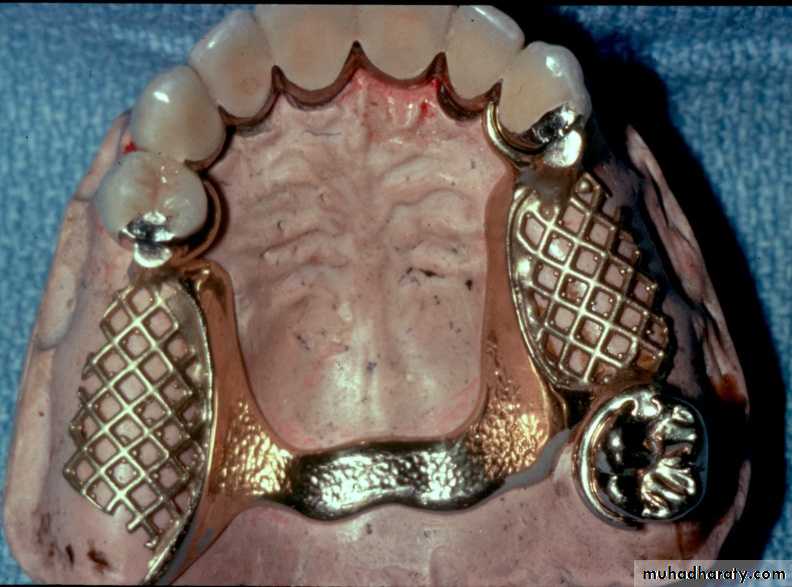

Bar Attachments

►Bar attachments consist of :A bar

Retentive clip(s)Definition of bar attachments

Advantages of Bar Attachments

* Excellent retention & stability for the prosthesis.* The bar acts as an indirect retainer & provides vertical support for the prosthesis preservation of the alveolar bone.

* Rigid splinting & constant mechanism of abutment stabilization

Requirements of Bar Attachments

** Adequate interocclusal

distance**Adequate clearance beneath

the bar

** Adequate Bony support

** Bar should follow ridge

Bar Joints

Bar Units* Resilient version

* Some rotational movement

between the bar & the sleeve

more R.R support

Less torque on teeth

* Rigid version

* provides rigid fixation – no

movement between the bar &

the sleeve indicated

when saddle gap is long

Classification of Bar Attachments

► Dolder bar attachment

ResilientRigid